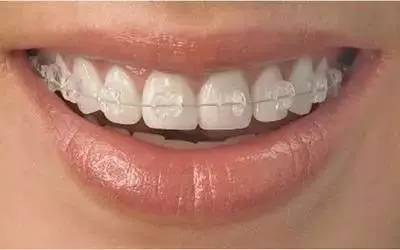

3美国3M透明托槽矫正

技术特点:

性价比高,比隐形矫正更经济,比金属托槽矫正更美观。

舒适,陶瓷矫治器表面光滑圆润,佩戴无异物感和粘。

隐形美观,玻璃陶瓷制作,呈乳白色半透明,与牙齿色泽一致。

方便快捷,佩戴舒适,拆卸方便,复诊次数减少,更节省时间。

透明、轻薄、美观、无异物感、正畸疗程短、佩戴更方便。